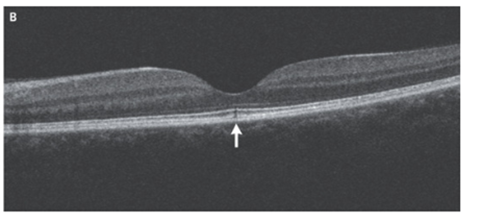

左黄斑の光干渉断層撮影法(OCT)施行。中心窩の光受容体の内側と外側の部分および網膜色素上皮の咬合帯の不連続性を認めた(矢印部位)。

右のOCTは正常だった。